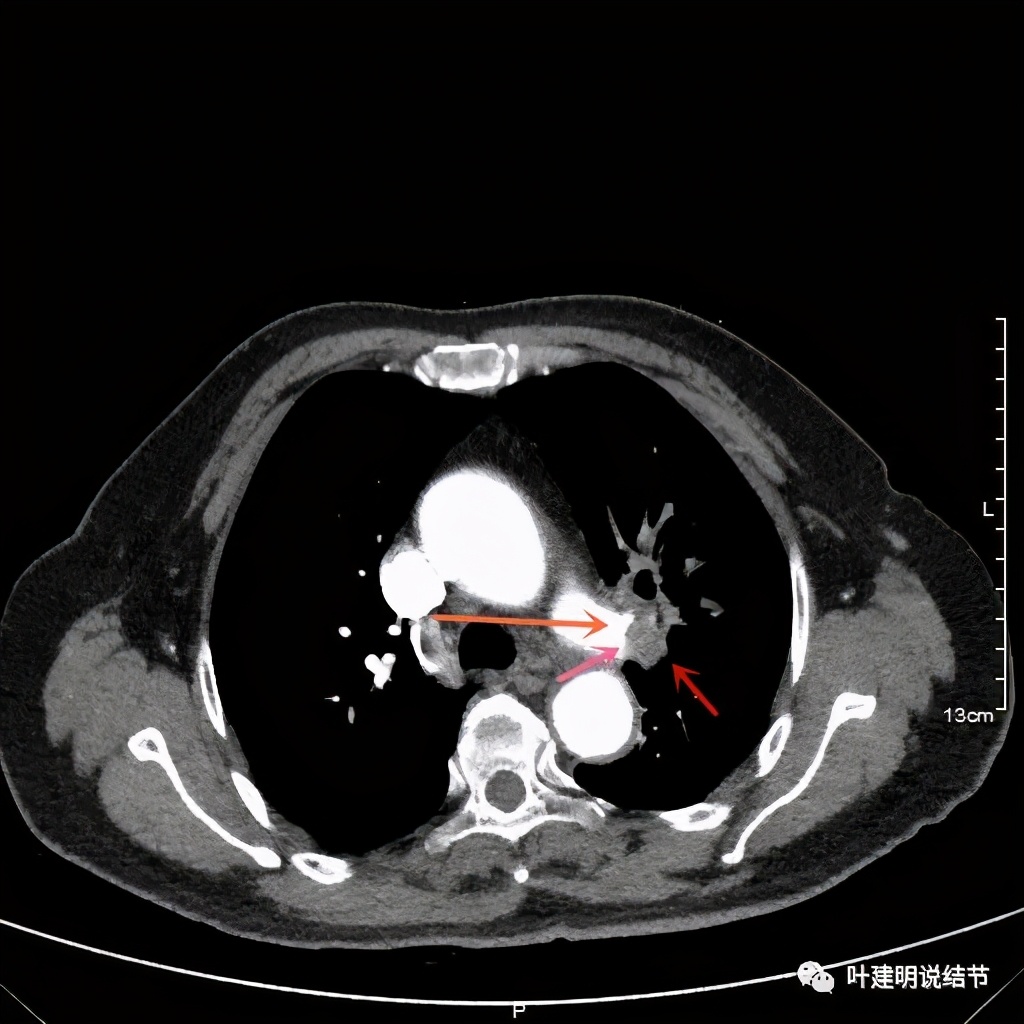

上图示肿瘤部位仍与肺动脉关系密切,似乎未能脱开,红色示肿瘤处

我样的治疗效果,显然超出了我们之前的预期,那么接下来拟选择行手术治疗,初定左上叶袖式肺叶切除加淋巴结清扫,但因为肺门区仍有软组织影,与肺动脉的关系仍密切,肿瘤与肺动脉间能否游离开来还是未知数,但至少得努力争取,鉴于患者年纪虽大,肺功能指标尚可,血气分析也基本正常,所以与患方沟通后确定行手术探查,但也也说明有万一全肺切除的可能(虽然这种可能性较小)。